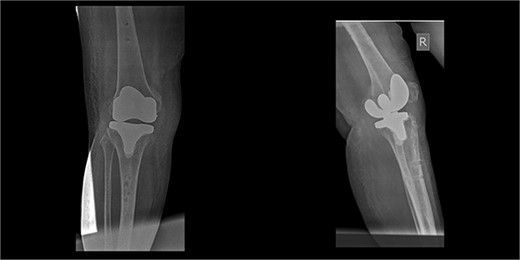

An 86-year-old female patient with a body mass index (BMI) of 31.2 presented to our outpatient department with severe right knee pain. Physical examination revealed a mechanical block of the knee, limiting its range of motion (ROM) between 10° and 55° of flexion. Plain knee radiographs showed grade 4 knee osteoarthritis (OA) in the Kellgren–Lawrence scale (Fig. 1).